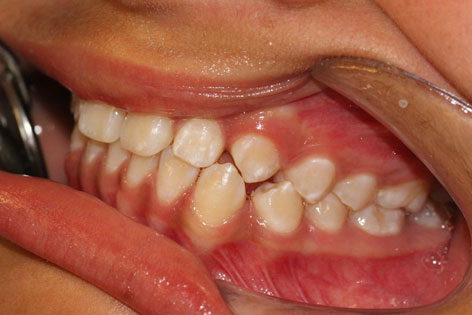

CASE REPORT A 12-year-old girl visited the Odontology Department at the Madrid Complutense University (UCM) for a check-up. A case history and clinical examination showed permanent dentition, mild class II bilateral canine, general enamel mineralisation defects (Figure 1) and possible wear facets in some teeth that were more marked in permanent maxillary right lateral (Figure 2). She presented no signs of muscle hypertrophy, although she experienced pain upon palpation of the masticatory muscles. Intra- and extra-auricular static and dynamic palpation of both TMJs was painful. A periapical X-ray of permanent maxillary right lateral showed a greater condensation of the bony ridge between permanent maxillary right lateral and permanent maxillary right canine and a broadening of the periodontal ligament in permanent maxillary right lateral, but no fracture lines or infection foci. An occlusal analysis was performed using a semi-adjustable articulator (Dentatus) and the Lauritzen Gnathological System in light of suspected CMD (Figure 3). The results of this study showed that the maximum intercuspation (MI) did not coincide with the centric relation (CR); there was a lack of canine guidance on the right side which was being provided by permanent maxillary right lateral and permanent mandibular right lateral, thus coinciding with the wear facets (Figure 4). The parents were asked to complete a questionnaire designed by us containing questions regarding the various CMD risk factors identified in the literature consulted. This showed that the patient presented headaches and parafunctional habits, her teeth were sensitive to cold stimuli and that she was a nervous child. These findings allowed us to confirm the presence of a compensated CMD, in other words the examination detected signs of dysfunction but the patient did not yet exhibit any symptoms. To prevent decompensation of the CMD, the patient was recommended to follow a series of preventive measures based on the findings reported in the literature consulted. These measures included eliminating parafunctional habits (nail-biting, chewing pens, chewing gum), avoiding stress and attempting not to sleep on her right-hand side to avoid using the tooth presenting the most marked wear facet (12). She was also advised to undergo orthodontic treatment to achieve correct canine guidance and a stable occlusion around the centric relation. DISCUSSION The patient presented all the risk factors proposed to cause CMD by the majority of authors. Although the incidence of this syndrome is higher in females (2,4,6,10) , the reason why some women are more susceptible to musculoskeletal pain, especially during the early stages of puberty, remains unknown (11). The parafunctional habits presented by the patient (teeth-clenching, nail-biting and chewing pens and gum) are considered to be etiological factors for CMD, especially amongst the young (2,3,5,12,13,14) . Our patient presented occlusal alterations, including the absence of a bilateral canine guidance, multiple non-working-side contacts, diastemas in various locations and an absence of concordance between the centric relation and the maximum intercuspation. Various studies have suggested occlusal anomalies to be classical etiological factors in the development of CMD(15) . CONCLUSSIONS - This paper describes an adolescent with signs of CMD that could be overlooked or mistaken for another condition. Therefore, a detailed case history and clinical examination should be performed in children and young people in order to ensure an early diagnosis of CMD. - The weakest component of our patient's SS was the dentition (generalised demineralisation). As a result, the first sign of CMD was wear facets. - Orthodontic treatment to achieve an appropriate condyle fossa position is particularly suitable for preventing the development or decompensation of a CMD in the event of occlusal alterations. Parafunctional habits in children should be eliminated and psychological factors that may lead to CMD in pubescent children should be controlled, as well.  Figure 1 Occluded dental arches showing the generalised enamel defects.  Figure 2 Wear facet in permanent maxillary right lateral due to absence of right canine guide  Figure 3 Casts mounted in the articulator using the Lauritzen Gnathological System.  Figure 4 Occlusal analysis showing that, on the right side, guidance is provided by permanent maxillary right lateral and permanent mandibular right lateral .   REFERENCES 1. Thilander B, Rubio G, Pena L, de Mayorga C. Prevalence of temporomandibular dysfunction and its association with malocclusion in children and adolescents: an epidemiologic study related to specified stages of dental development. Angle Orthodontist 2002; 72 (2): 146-54. 2. Pereira LJ, Pereira-Cenci T, Del Bel Cury AA, Pereira SM, Pereira AC, Ambrosano GM, Gaviao MB "Risk Indicators of Temporomandibular Disorder Incidences in Early Adolescence". Pediatr Dent 2010; 32(4):324-8. 3. Seraj B, Ahmadi R, Mirkarimi M, Ghadimi S, Beheshti M Temporomandibular Disorders and Parafunctional Habits in Children and Adolescence: A Review. J Dent 2009;6(1):37-45. 4. Nilsson IM, Drangsholt M, List T "Impact of Temporomandibular Disorder Pain in Adolescents: Differences by Age and Gender". J Orofac Pain 2009; 23 (2): 115-22. 5. Michelotti A, Coffi I, Festa P, Scala G, Farella M. Oral parafunctions as risks factors for diagnostics TMD subgroups. J Oral Rehabil 2010;37:157-62. 6. Miller JR, Mancl L "Risk factors for the occurrence and prevention of temporomandibular joint and muscle disorders: Lessons from 2 recent studies". Am J Orthod Dentofacial Ortop 2008; 134(4):537-42. 7. Greene CS. The etiology of temporomandibular disorders: Implications for treatment. J Orofac Pain 2001;15(2):93-105. 8. Leresche L, Mancl LA, Drangsholt MT, Huang G, Von Korff M. Predictors of onset of facial pain and temporomandibular disorders in early adolescence. Pain 2007;129:269-78. 9. Pozo JJ, Pérez MD, Casado JR. Disfunción del aparato estomatognático. Semiología neuromuscular. Rev Eur Odonto-Estomatología 2004; 16 (3): 123-34. 10. Winocur E, Littnerusb D, Adamsusb I, Gavish A. Oral habits and their association with signs and symptoms of temporomandibular disorders in adolescents: a gender comparison. Oral Surg Oral Med Oral Pathol Oral Radiol Endod 2006;102:482-7 11. Ferreira CL, da Silva MA, de Felício CM "Orofacial Myofunctional Disorder In Subjects with Temporomandibular Disorder". Cranio 2009;27(4):268-74. 12. Emodi-Perlman A, Eli I, Friedman Rubin P, Goldsmith C, Reiter S, Winocur E. Bruxism, oral parafunctions, anamnestic and clinical findings of temporomandibular disorders in children. J Oral Rehabil 2012; 39; 126-35. 13. Cortese SG, Biondi AM. Relationship between dysfunctions and parafunctional oral habits, and temporomandibular disorders in children and teenagers. Arch Argent Pediatr 2009;107(2):134-38. 14. Magnusson T, Egermark I, Carlsson G. A prospective investigation over two decades on signs and symptoms of temporo-mandibular disorders and associated variables. A final summary. Acta Odontol Scand 2005;63(2):99-109. 15. American Academy of Pediatric Dentistry Clinical Affairs Committee-Temporomandibular Joint Problems in Children Subcommittee; American Academy of Pediatric Dentistry Council on Clinical Affairs. "Guideline on acquired temporomandibular disorders in infants, children and adolescents". Pediatr Dent 2011:Special Issue 33 (6): 248-53.